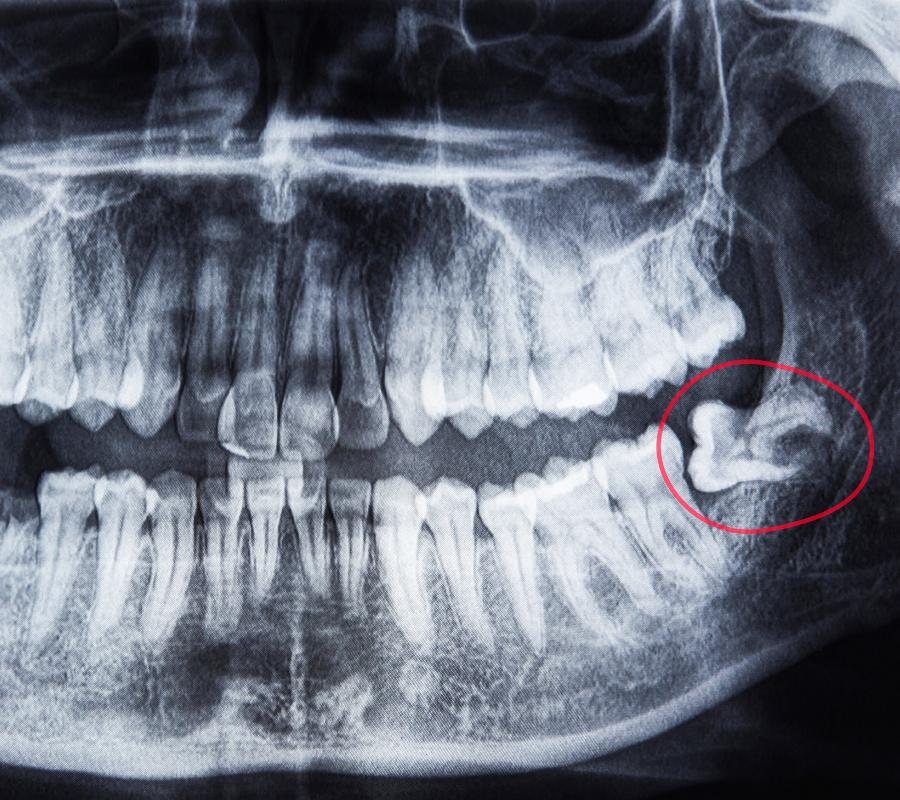

• Avoid Painful Impactions: Impacted wisdom teeth can lead to pain, swelling, and infections. Our Palmer team specializes in preventing and treating these complications with precise extractions.